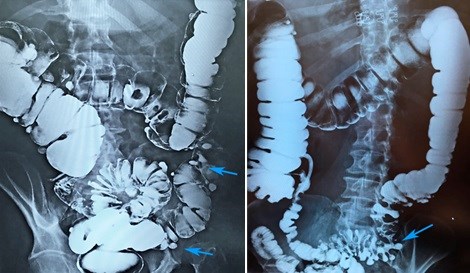

«Золотым стандартом» диагностики дивертикулярной болезни является ирригоскопия. Этот метод позволяет определить количество дивертикулов, их точное местоположение, размеры и форму. Суть процедуры заключается в введении рентгенконтрастного препарата в толстую кишку, после этого выполняется серия рентгенологических снимков, позволяющих оценить состояние толстой кишки. На представленных фотографиях стрелками указаны устья дивертикулов толстой кишки. Синими стрелками мы отметили множественные дивертикулы ободочной кишки. Именно так они выглядят при компьютерной томографии.

Ирригоскопия. Дивертикулез толстой кишки

На рентгенологических снимках, выполненных при ирригоскопическом исследовании, отчетливо видны множественные дивертикулы ободочной кишки. Они выглядят как мешочки, заполненные рентгеноконтрастным препаратом.